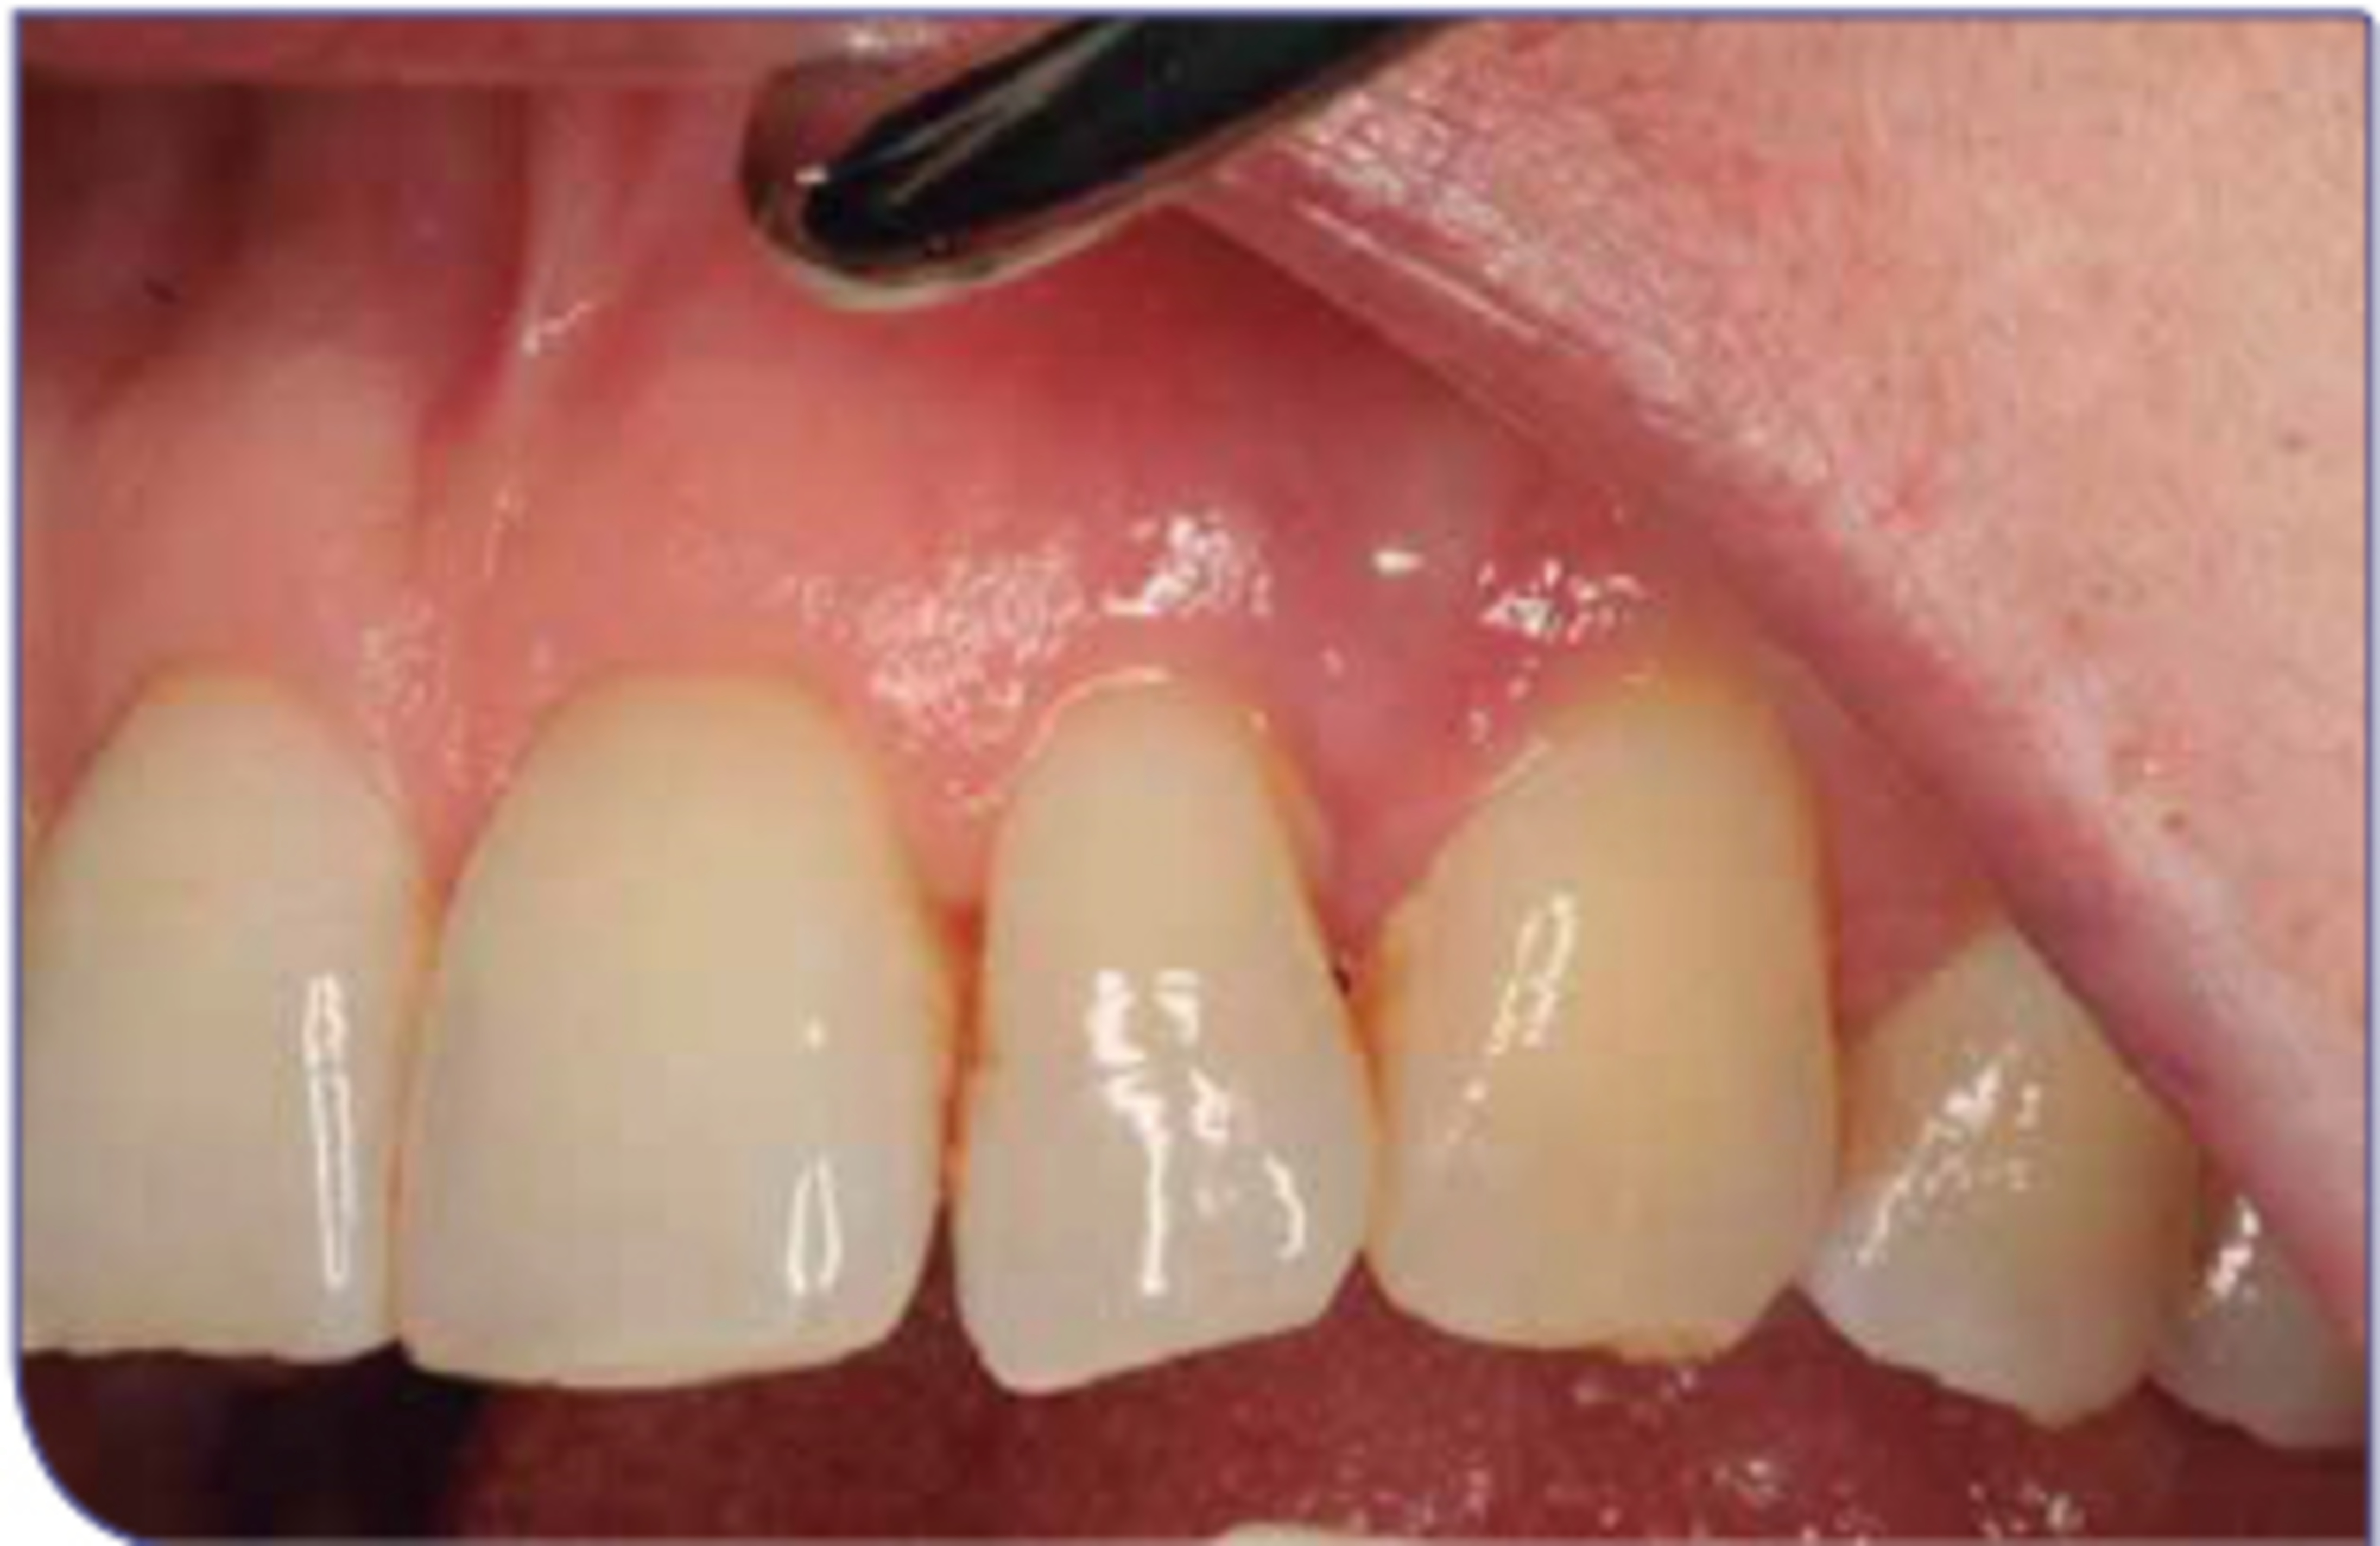

Image C1:6 5 Days Post-Operative (Tooth 22)

Rapid wound healing and reformation of normal ketarinised gingival tissue at the surgical site.